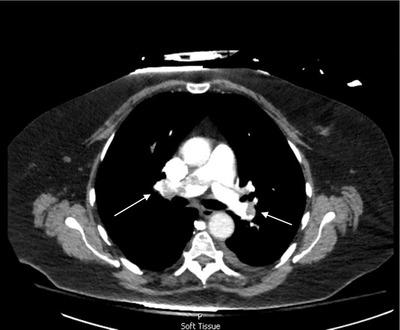

Elderly woman with shortness of breath.